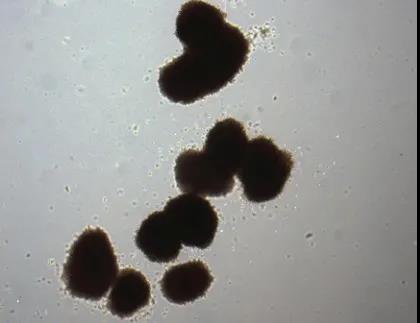

地中海貧血患者小米(化名)做完臍帶血移植后情況良好。她使用的臍帶血,來自于母親再次懷孕生下的兩位雙胞胎弟弟